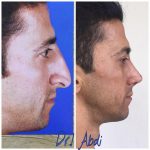

– متخصص جراحی فک , پلاستیک صورت و بینی

جراحی فک , پلاستیک , صورت وبینی

جراحی ترمیمی و زیبایی فک و صورت و جمجمه و گردن